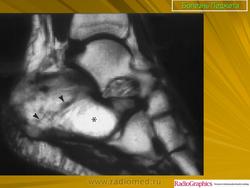

Литическая фаза.

Смешанная фаза.

Принято различать три фазы развития П. б.: очаговая интенсивная резорбция кости (остеолитическая, или деструктивная, фаза), смешанная фаза, когда наряду с рассасыванием кости идут процессы новообразования ее, и остеобластическая, или склеротическая, фаза с образованием типичных мозаичных структур.